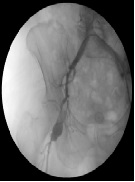

Endovascular Solution of a Post-Operative Iliofemoral Pseudo-Aneurysm: Case Report

E. Scudieri*, R. Adornetto, E. Orlandelli, A. Disabato, V. Dorrucci